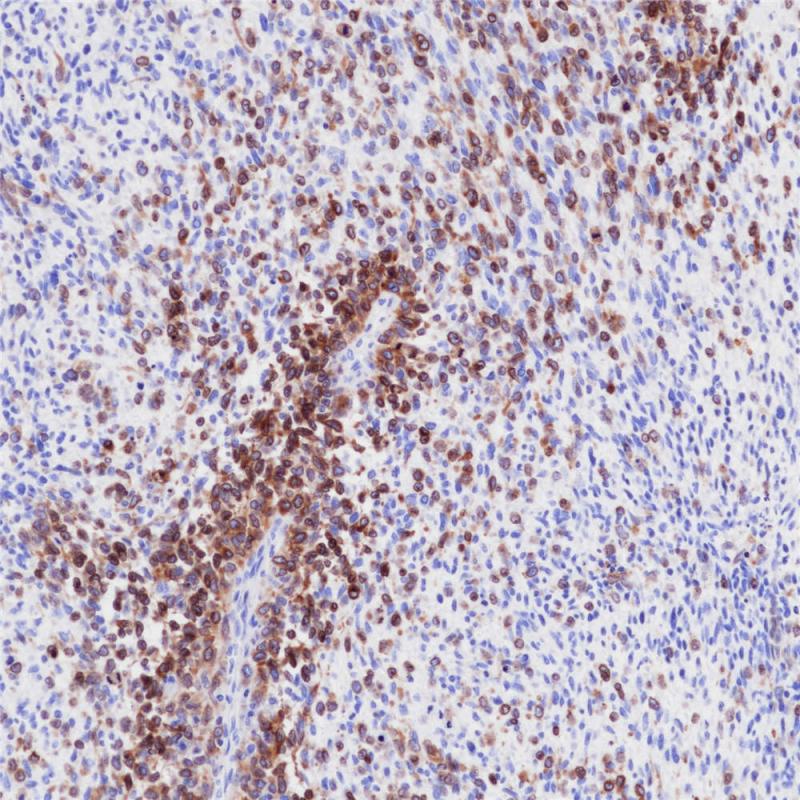

Melan A是由118个氨基酸组成的跨膜蛋白,在皮肤,视网膜和大多数的黑色素细胞以及黑素瘤和血管平滑肌脂肪瘤中表达。 该抗体有助于黑素瘤和肾上腺皮质癌的分类以及血管平滑肌脂肪瘤的分类。

阳性对照

黑色素瘤

亚细胞定位

细胞质